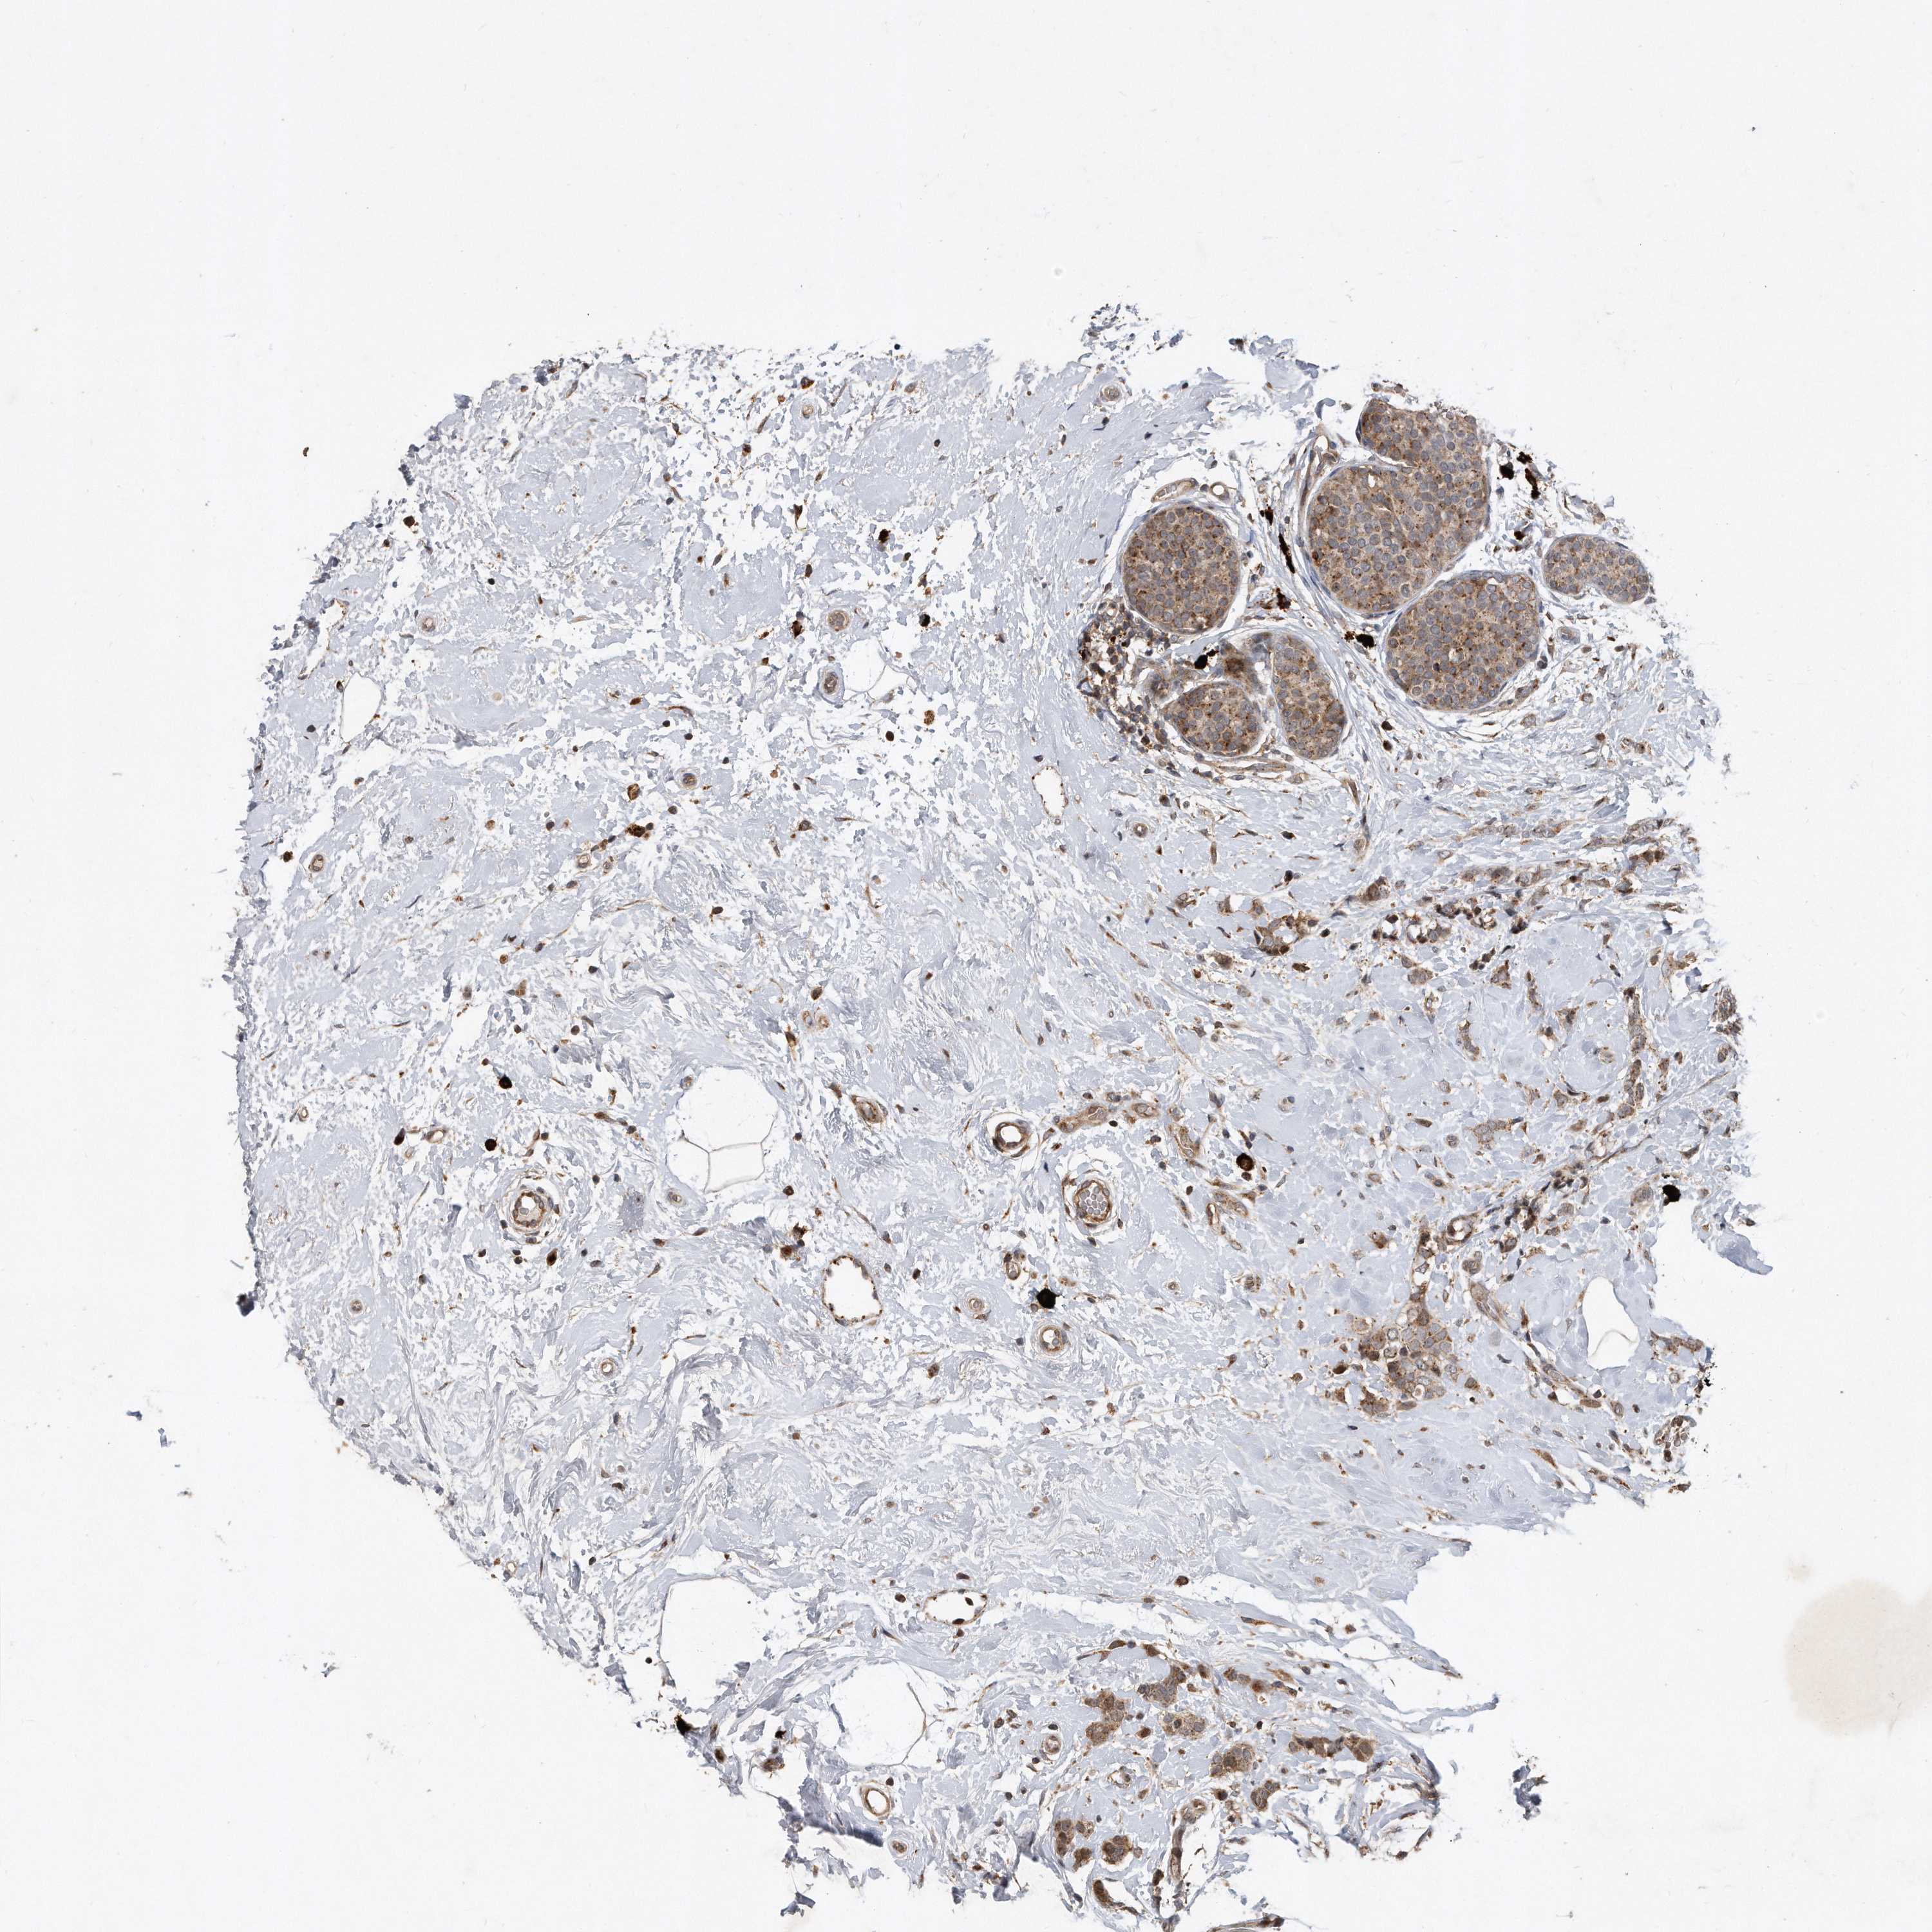

CANCER BREAST CANCER Show tissue menu

BRCA TCGA BRCA VALIDATION PROTEIN EXPRESSION